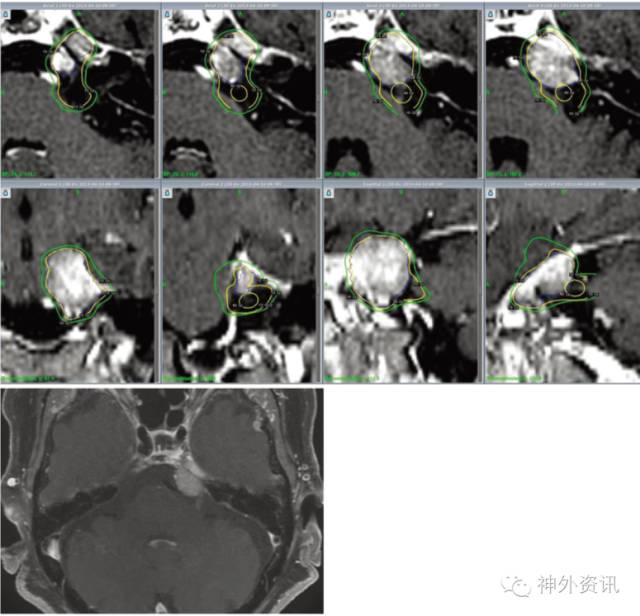

图1. 1例76岁女性患者。MRI成像显示,左侧小脑桥脑角区有1个边界清晰的肿瘤,诊断为脑膜瘤;肿瘤体积约4cm3。上图示:蓝色线条描绘肿瘤轮廓;50%等剂量线(外围黄线)的肿瘤周边放射剂量为13Gy;里面的黄线圈代表覆盖三叉神经REZ区40Gy的剂量线,REZ区的最大剂量为80Gy;绿色线圈是10Gy剂量线,代表暴露在10Gy下的脑干体积;最终,该患者的三叉神经痛由BNI(巴罗神经研究所疼痛评分)IV分下降至I分,未发生任何并发症。下图示:伽马刀治疗18个月后肿瘤无明显变化。

最终纳入15例患者,其中男性6例,女性9例;年龄45-79岁,中位数69岁(表1)。头颅MRI提示脑膜瘤11例、前庭神经鞘瘤3例和三叉神经鞘瘤1例;肿瘤体积0.1-4.9cm3,中位数1.7cm3。靶向肿瘤的放射剂量11-15Gy,平均13Gy;靶向三叉神经REZ区的放射剂量70-85Gy,平均80Gy。随访时间12-78个月,平均为38个月。伽马刀治疗后,起初有14例(93.3%)患者疼痛缓解,截止至随访结束时为13例(86.7%)疼痛缓解。随访1、3和5年的肿瘤无复发生存率分别为93%、83%和69%。3例患者出现永久性面部麻木;此外,15例均无面瘫、味觉功能改变等VII-VIII颅神经损伤症状以及躯体肌力损害和平衡障碍(表2)。脑干组织接受12Gy放射剂量的体积≤0.24 cm3。出现面部麻木患者与无面部麻木患者的脑干OARs值无明显统计学差异(图1)。